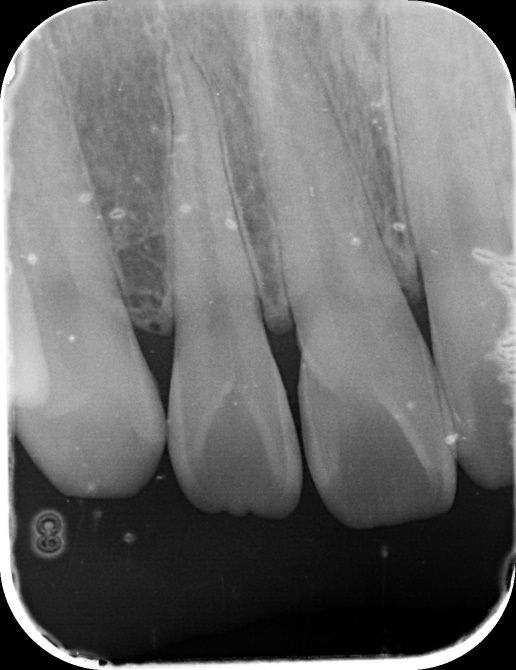

앞니 사이 인접면 충치가 있나요?(사진 첨부)

12, 11, 21, 22 번 4개 앞니 치아들에 대해서

1. 법랑질만 우식된 충치인가요? 아니면 상아질까지 우식된 충치인가요?

• 1번 째 사진

엑스레이 상으로는 11과 12번의 사이, 21과 22의 사이에 충치가 있는 것으로 보이는데 맞나요?

실제로 바람불어서 긁어봐야 판단이 설 것 같긴한데 일단 엑스레이만 봐서는 관리를 잘한다고 해서 진행을 멈출 사이즈의 충치는 아닌 것 같은데, 지금처럼 인접면 충치의 경우에는 충치부위에 기구접근이 안되기 때문에 딱 충치부분만 제거를 할 수가 없어요. 그래서 좀 더 커질때까지 두고 보자vs지금 치료를 하자 이렇게 나뉜 것 같은데 원래 정석적으로는 바로 치료를 하는게 맞긴 합니다만, 치료를 해서 얻는 것보다 정상치질을 더 제거해야해서 잃는 실이 더 많다고 판단이 되면 좀 더 있다가 하기도 합니다. 이런 애매한 경우는 환자분께서 결정을 하시면 될 것 같습니다.

1. 법랑질 수준에 국한된 충치입니다.

2. 심미적으로 해당 부위가 검게 보이지 않는다면 관리를 하면서 지켜볼 수도 있습니다. 다만 겉으로 보기에는 검게 보인다면 치료를 하는 것이 맞으며 이는 심미적인 이유 때문입니다.

3. 11, 21 모두 치아에 일부 충치가 보입니다. 따라서 2곳 모두 치료해야할 것으로 보입니다.

엑스레이 상으로는 충치가 크게 보이진 않습니다. 저정도라면 저도 일단은 관리를 잘하시면서 지켜보라고 할것같습니다.

사진으로 보기에는 초기 우식이 보이기는 합니다. 하지만 ㅣㅊ료여부는 육안으로 확인을 해야알수가 있어요.